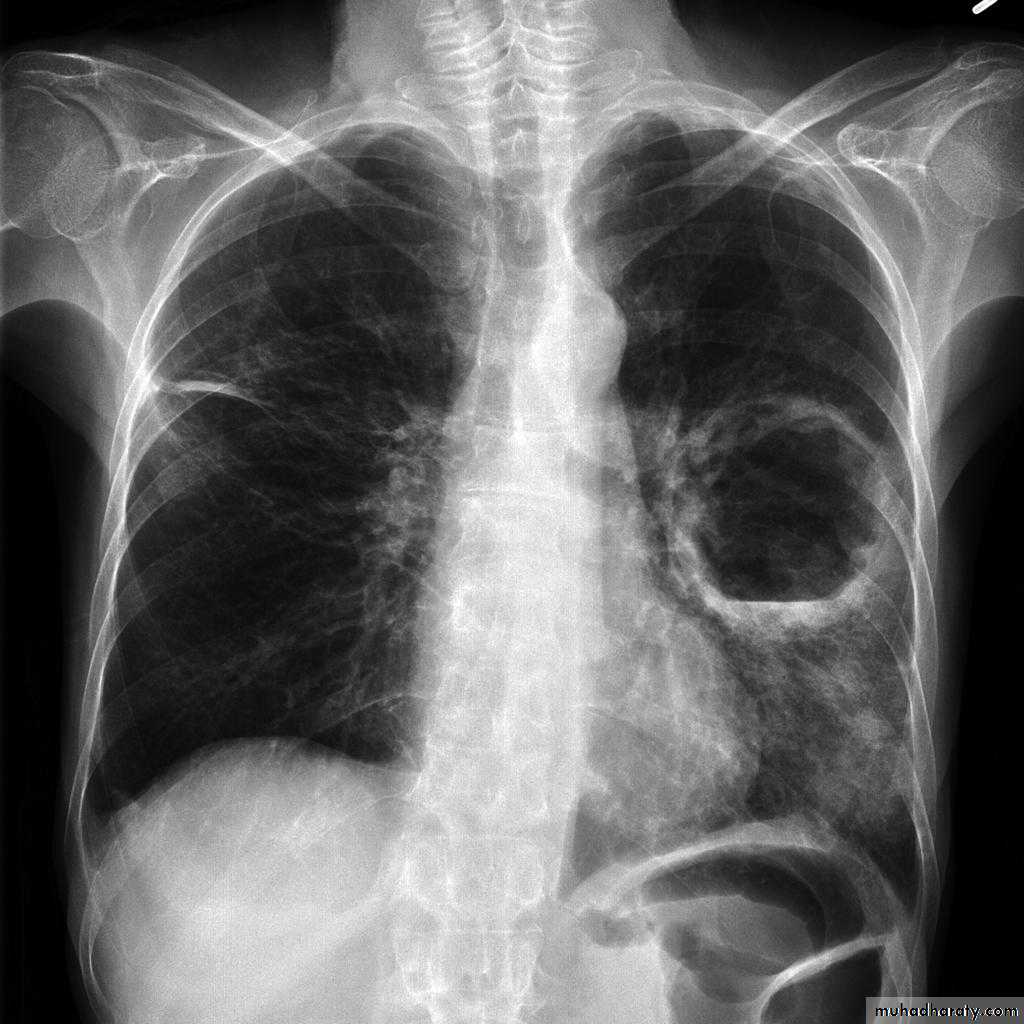

1-CXR:

PA and lateral views show effusion, air fluid level

CXR : Air fluid level is only seen in upright film

1-Cavitating lung carcinoma2- Infected lung cyst or bullae

3-TB

4- Bronchiectasis